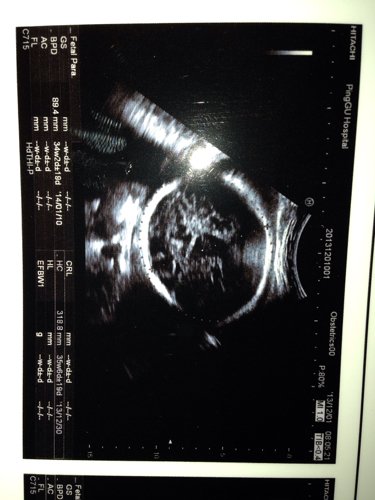

我怀孕34+2,今天检查医生说孩子头大,腿短,我还缺铁性贫血,我怕早产,我24周岁!想咨询孩子怎么 我怀孕34+2,今天检查医生说孩子头大,腿短,我还缺铁性贫血,我怕早产,我24周岁!想咨询孩子怎么样,多少斤了,会不会早产 点击展开 匿名用户 2013-12-02 00:10 为您推荐: 其他回答 病情分析: 你好,以双顶颈来判断胎儿的发育大小,只是一个参考性的数据。 指导意见: 在30周以后,允许有上下两周的误差,建议及时复查. 独水凡_xjeq 2013-12-02 09:53 相关问题 我怀孕34周两天,检查缺铁性贫血,怕孩子早产,不知道正常不正常,还说孩子头大,腿短 孕妇缺铁性贫血吃铁之缘片可以吗 是一位医生说的 可是上面写着保健食品不可代替药物 怀孕33周 股骨长径58mm 医生说会比正常人腿短点 这个严重吗?